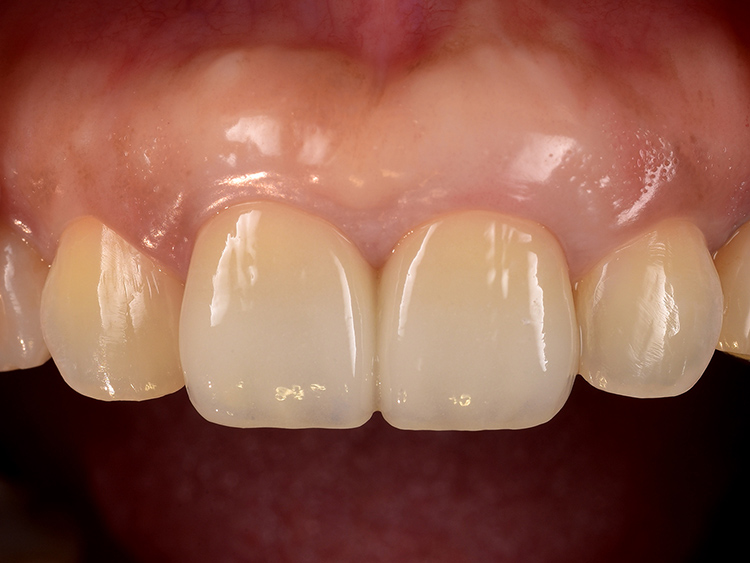

治療完了後の状態

治療後の状態です。

厚みとハリのある健全な歯周組織が回復しました。今回は両歯ともに歯根の長さが短いことから、互いに負担を分散し安定性を高めるため、連結冠としました。これにより咀嚼機能が向上し、患者さんは安心して食事ができるようになりました。